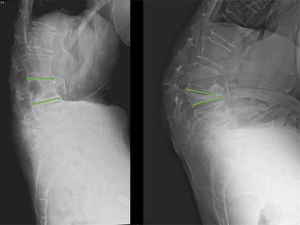

Fig. 4 shows a clinical case of MIS instrumentation of a patient with sagittal imbalance due to vertebral fractures. Note the cement augmentation of the screws to increase screw strength.

Male, 71 years old, who suffered a fall from standing height in January 2023. Since then, he has presented with dorsolumbar pain. Images A and B show a teleradiograph showing the significant sagittal imbalance caused by multiple vertebral fractures, resulting in hyperkyphosis. Images C and D show the first postoperative X-ray. Long posterior instrumentation was performed, with minimally invasive techniques and cement augmentation of the most cranial and caudal screws. Images E and F show the first postoperative teleradiograph, at one month, where the restoration of sagittal balance is evident.

In cases with fractures requiring surgical treatment, the development of minimally invasive techniques assisted by navigation or robotic systems42 can increase the accuracy of pedicle screw placement. In addition, there are technologies based on artificial intelligence or augmented reality with which it is possible to improve the classic surgical result by intraoperative measurement of the deformity and moulding of the rod to correct the fracture.43

Fig. 5 shows the application of new technologies to these procedures.